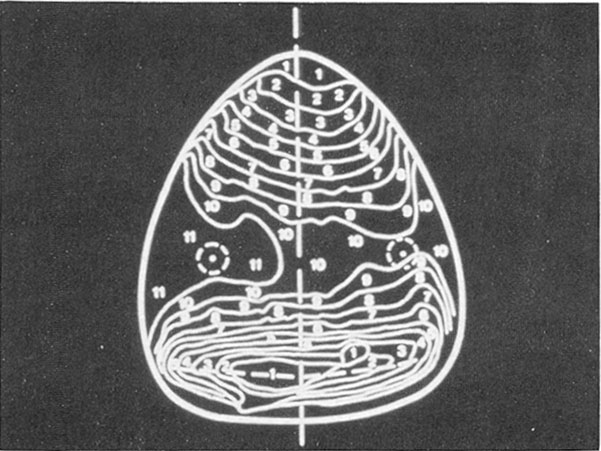

With the basic bracket design and the desired criteria in mind, it was necessary to determine if lingual tooth anatomy and intertooth relationships were amenable to a lingual edgewise straight-wire approach. To confirm the feasibility of such an approach, topographical contour maps of lingual anatomy were made from models of several finished orthodontic cases (Fig. 1). It became apparent that, with the exception of short clinical crowns, lingual morphology presented no great obstacles to establishing a straight archwire plane in both maxillary and mandibular arches. It was also observed that this plane was parallel to the occlusal plane in most cases.

Fig. 1 Topographical mapping of maxillary arch.